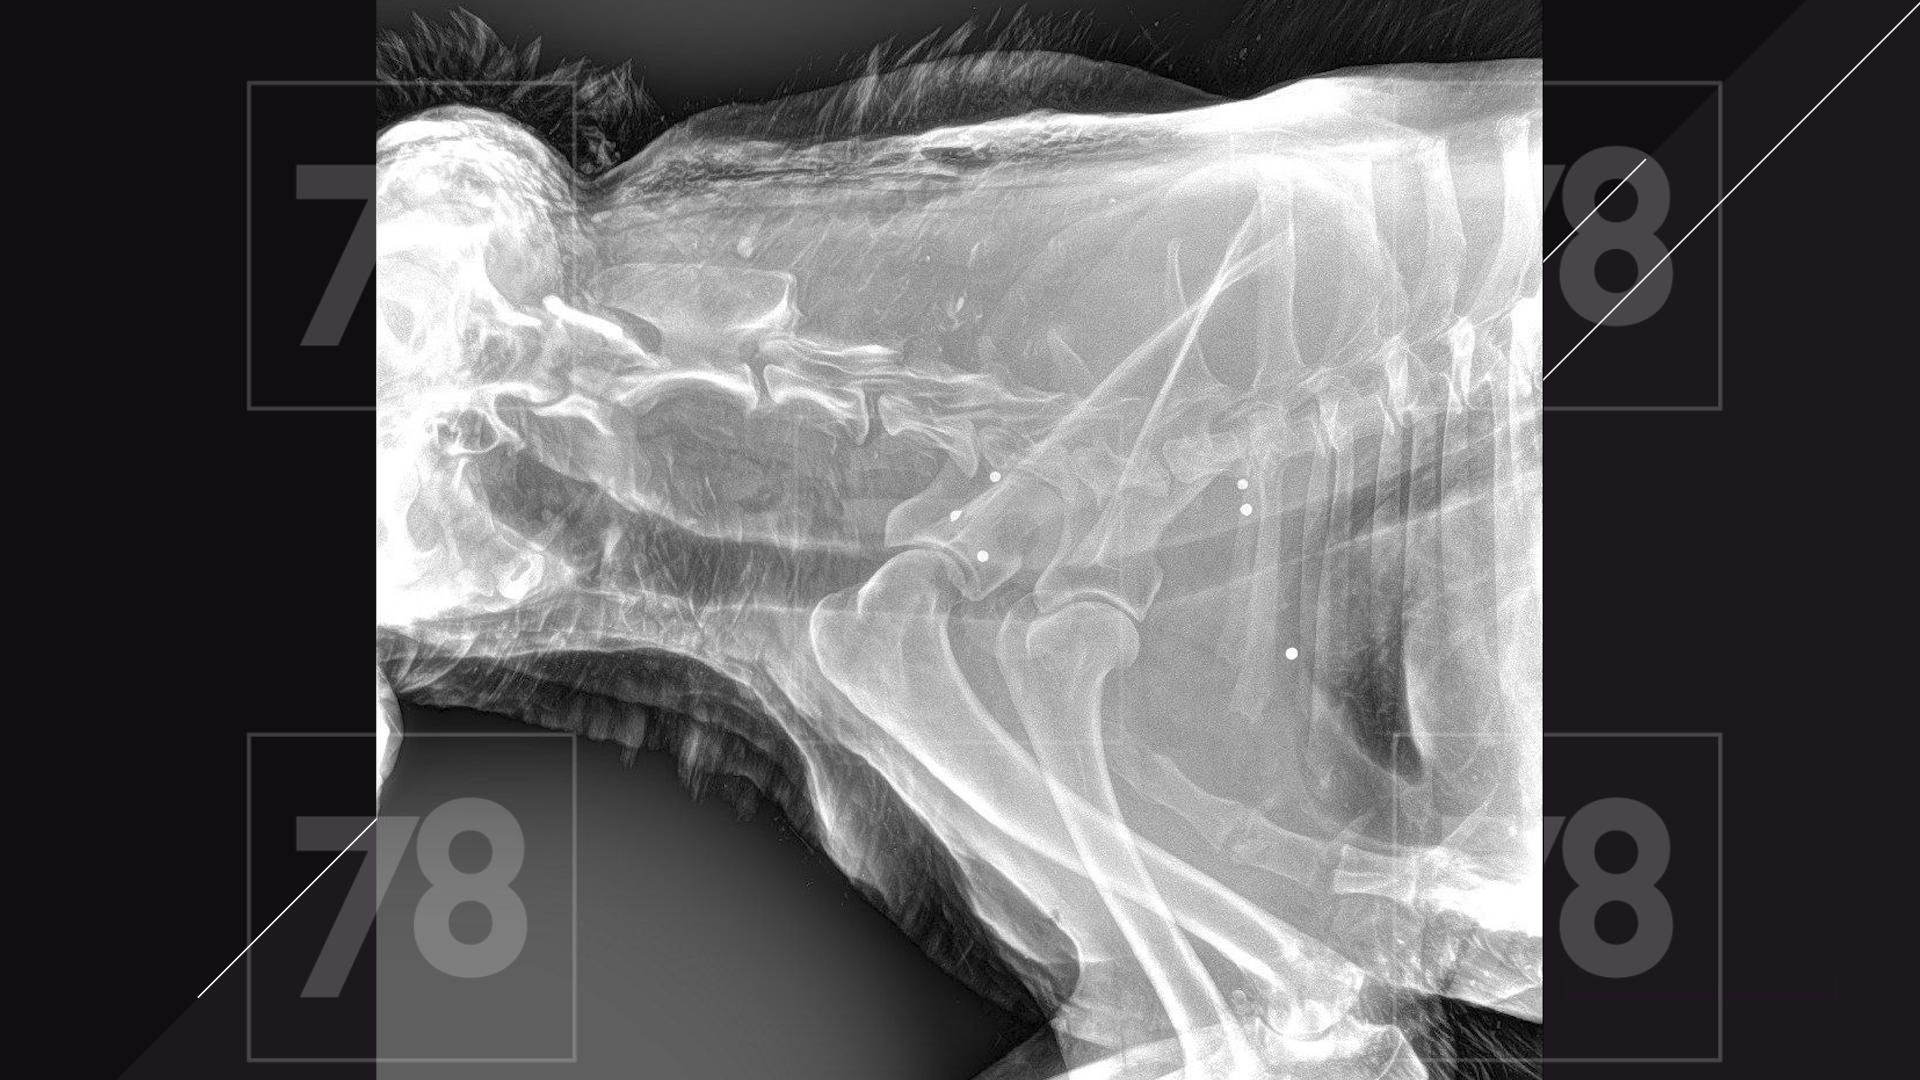

Врачи обнаружили у собаки множественные ранения пулями, как свежие, так и старые.